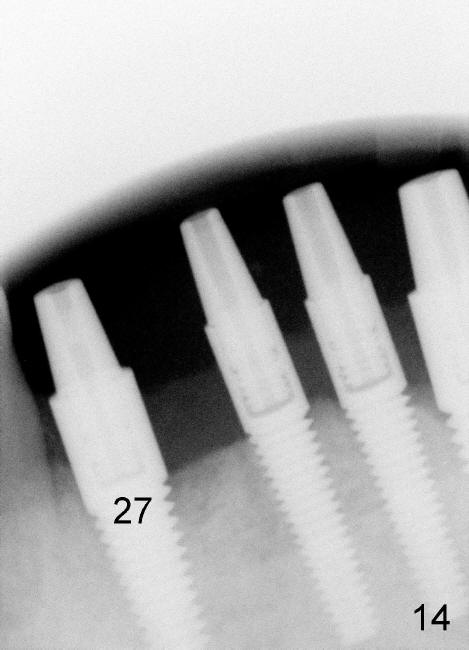

The 4 anterior implants appear to have been osteointegrated 5 months postop (Fig.14,15). More gingiva has covered the top portion of the implants (Fig.16). Ball abutments are placed for an overdenture (Fig.17).